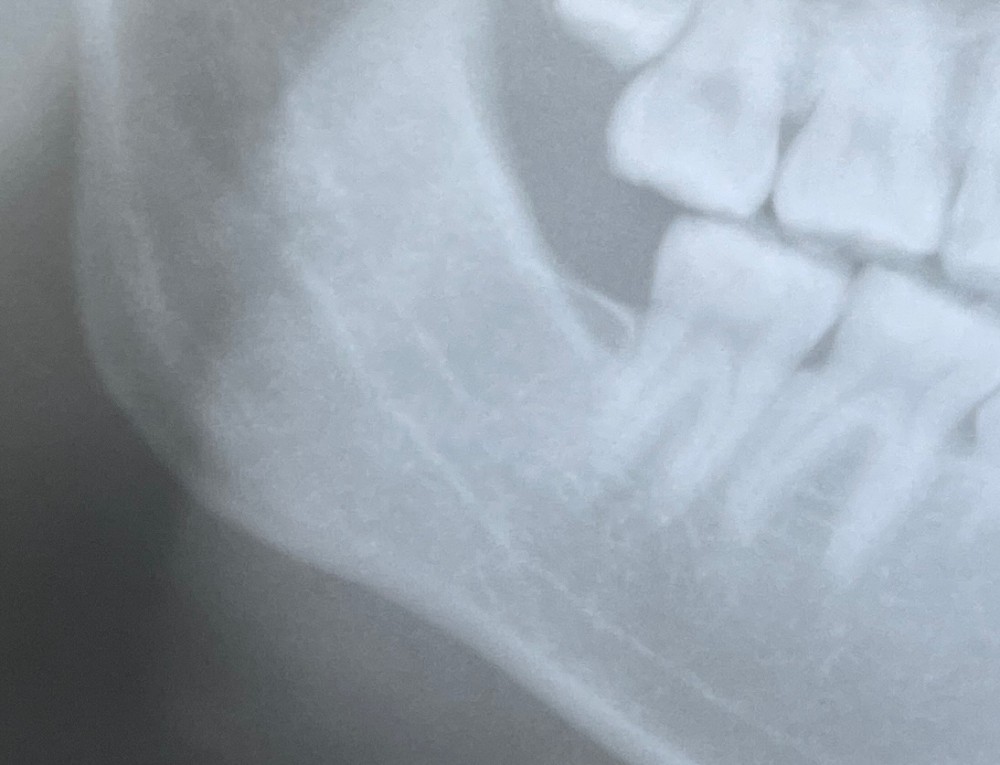

その際のエックス線写真がこちらです。

骨折の線が、黒いラインとして見えるのがわかります。